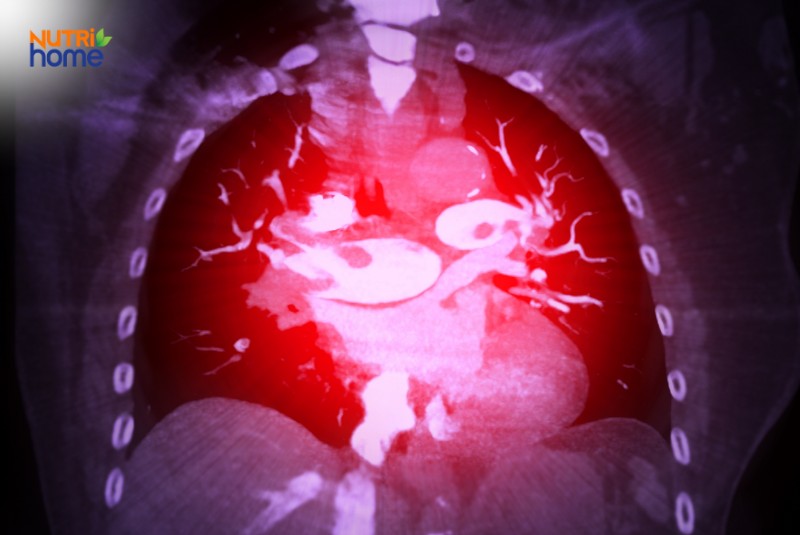

Minh họa hình ảnh chụp CT mạch phổi giúp chẩn đoán thuyên tắc phổi